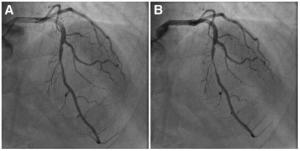

1.冠脉造影

若发现冠脉收缩期狭窄或合并舒张期松弛延迟现象,则提示有心肌桥存在。但冠脉造影只能检出那些对冠脉血流产生显著影响的心肌桥。心肌桥的检出与其长度、肌桥纤维的走行方向、心肌桥与相关动脉间的组织有关。有些心肌桥由于其近端的冠脉几乎完全闭塞或动脉粥样硬化产生的固定性狭窄限制了冠脉的血流灌注而掩盖了其收缩期狭窄,或由于血管痉挛的存在,造影很难发现。冠脉造影常不能发现心肌桥处的动脉粥样硬化性狭窄。